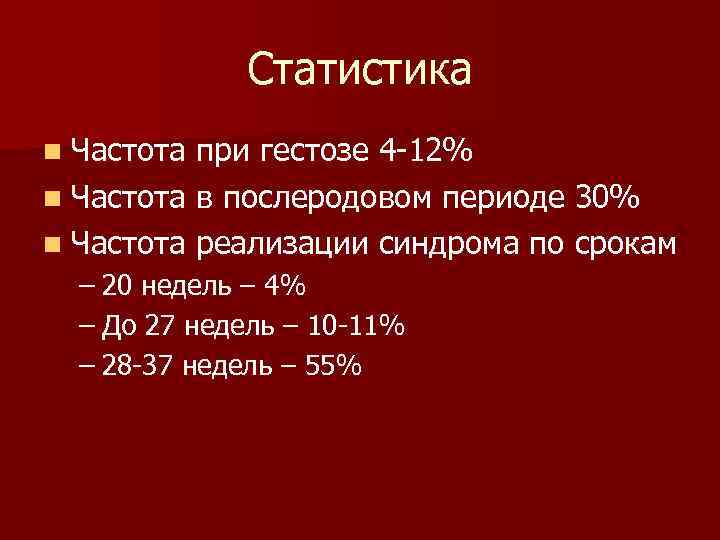

Статистика n Частота при гестозе 4 -12% n Частота в послеродовом периоде 30% n Частота реализации синдрома по срокам – 20 недель – 4% – До 27 недель – 10 -11% – 28 -37 недель – 55%

Статистика n Частота при гестозе 4 -12% n Частота в послеродовом периоде 30% n Частота реализации синдрома по срокам – 20 недель – 4% – До 27 недель – 10 -11% – 28 -37 недель – 55%